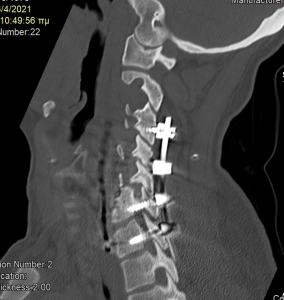

Στη συνέχεια, αφαίρεση της πρόσθιας πλάκας, ολοκλήρωση της σωματεκτομής Α5 & Α6, απελευθέρωση του νωτιαίου μυελου, πρόσθια δισκεκτομή Α7/Θ1 και τοποθέτηση πρόσθιας πλάκας Α4-Θ1.

Στη συνέχεια γυρίσαμε την ασθενή σε ύπτια θέση και αφού αφαιρέσαμε την παλαιά πλάκα, αποκαθηλώνοντας τον οισοφάγο, ολοκληρώσαμε τη σωματεκτομή και απελευθερώσαμε τα νευρικά στοιχεία και από μπροστά. Μια και δεν ήταν δυνατή η στήριξη της πλάκας στον Α7, αλλά ούτε και θέλαμε να καταλήξουμε ένα τεράστιο χάσμα, αποφασίσαμε να διατηρήσουμε τον Α7 και να διενεργήσουμε πρόσθια δισκεκτομή Α7/Θ1, καθηλώνοντας τελικά την πλάκα στον Α4, Α7 και Θ1 σπόνδυλο.